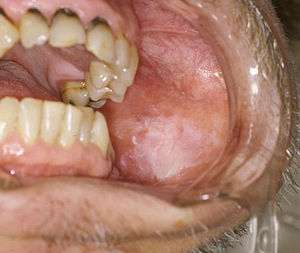

Oral cancer on the side of the tongue, a common site along with the floor of the mouth | |

It may arise as a primary lesion originating in any of the tissues in the mouth, by metastasis from a distant site of origin, or by extension from a neighboring anatomic structure, such as the nasal cavity. Alternatively, the oral cancers may originate in any of the tissues of the mouth, and may be of varied histologic types: teratoma, adenocarcinoma derived from a major or minor salivary gland, lymphoma from tonsillar or other lymphoid tissue, or melanoma from the pigment-producing cells of the oral mucosa. There are several types of oral cancers, but around 90% are squamous cell carcinomas,[3] originating in the tissues that line the mouth and lips. Oral or mouth cancer most commonly involves the tongue. It may also occur on the floor of the mouth, cheek lining, gingiva (gums), lips, or palate (roof of the mouth). Most oral cancers look very similar under the microscope and are called squamous cell carcinoma, but less commonly other types of oral cancer occur, such as Kaposi's sarcoma.

A premalignant (or precancerous) lesion is defined as "a benign, morphologically altered tissue that has a greater than normal risk of malignant transformation." There are several different types of premalignant lesion that occur in the mouth. Some oral cancers begin as white patches (leukoplakia), red patches (erythroplakia) or mixed red and white patches (erythroleukoplakia or "speckled leukoplakia"). Other common premalignant lesions include oral lichen planus (particularly the erosive type), oral submucous fibrosis and actinic cheilitis.[9] In the Indian subcontinent oral submucous fibrosis is very common. This condition is characterized by limited opening of mouth and burning sensation on eating of spicy food. This is a progressive lesion in which the opening of the mouth becomes progressively limited, and later on even normal eating becomes difficult. It occurs almost exclusively in India and Indian communities living abroad. The overall prevalence of oral potentially malignant disorders in the Middle East was 2.8%. Lichen planus/lichenoid lesions were the most common lesions (1.8%) followed by leukoplakias (0.48%), chronic hyperplastic candidiosis (0.38%), and erythroplakia (0.096%). Smoking, alcohol, and age (>40 years) were the main identifiable risk factors.[10]